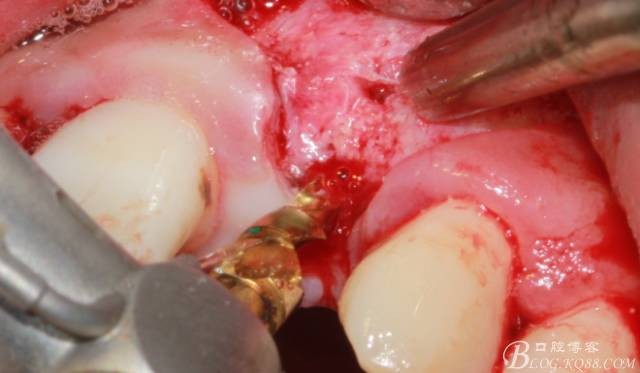

徹底搔刮拔牙窩,偏腭側(cè)備洞

順利植入植體,扭力30N。三壁骨,感覺(jué)美美的